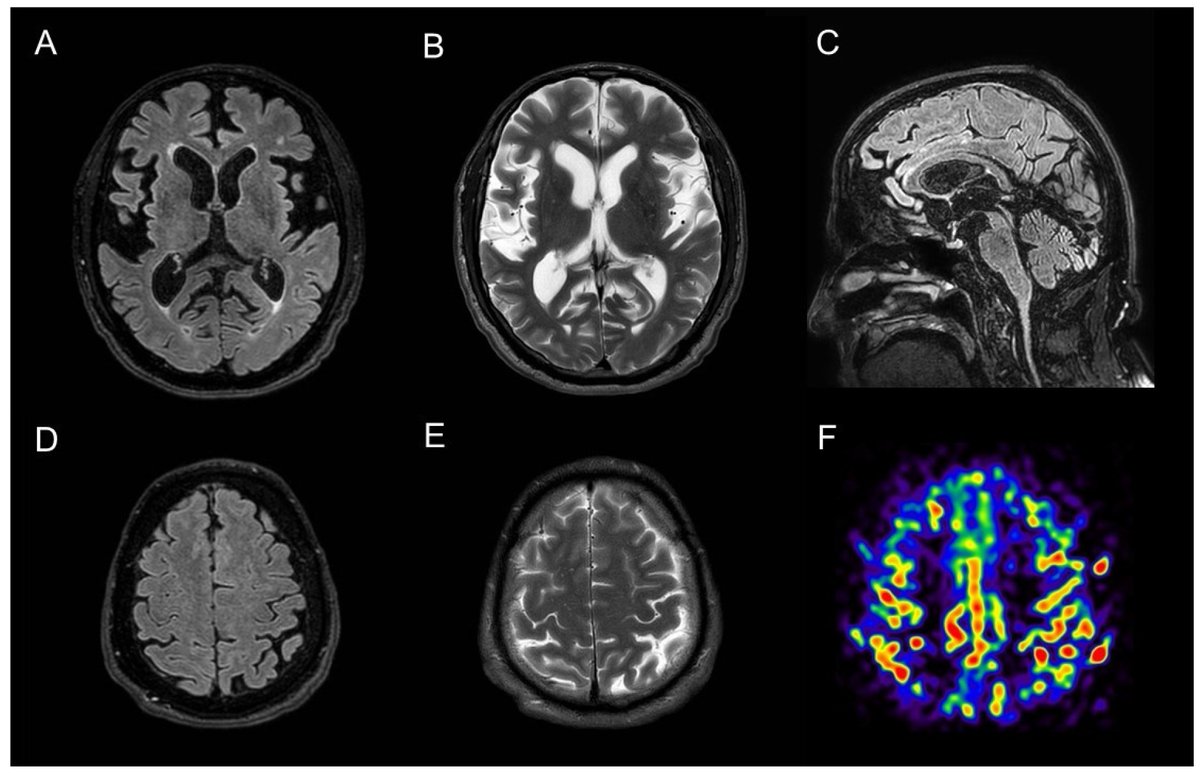

First, some context. Two proteins build up in Alzheimer's brains: AMYLOID and TAU.

We've known for years that sleep clears toxic waste from the brain (amyloid, tau - proteins linked to Alzheimer's).

The study used UK Biobank data with 1,987 participants developing dementia over 10 years (mean age at onset: 74.6 years).